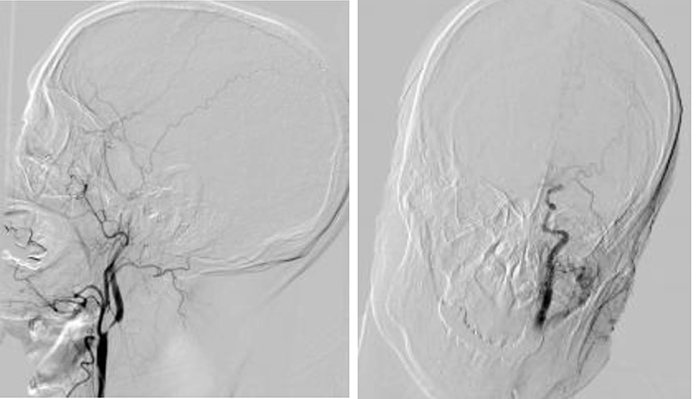

▲患者脑血管造影提示左侧颈内动脉C1段次全闭塞及左侧大脑中动脉M1段闭塞

林宝荣主任医师迅速向神经内科主任叶端玲汇报患者病情,根据指示首先为患者行静脉溶栓治疗,并火速联系介入诊疗组直接行脑血管介入治疗。 神经内科主任 叶端玲 急性脑梗死最有效的治疗方式,是在较短时间内开通闭塞血管,静脉溶栓和机械取栓是最常见的治疗手段。 考虑患者为急性脑梗死,处于静脉溶栓时间窗内,首先予以阿替普酶静脉溶栓,由于患者梗死面积大,静脉溶栓再通率低,遂为其行脑血管介入治疗。 抢救刻不容缓! 神经内科介入诊疗组成员 卢红腾主治医生 与家属沟通手术风险及必要性 取得家属同意后 随即给予急诊取栓治疗 患者的血管情况不容乐观,由于左侧颈内动脉C1段次全闭塞及左侧大脑中动脉M1段闭塞,可能引起肢体瘫痪、昏迷、甚至死亡,加上手术时间长,再通率低,这对医生的体力和技术都是极大的挑战! 经过充分的术前准备,陈金龙主任医师、卢红腾主治医师详细制定了手术方案。